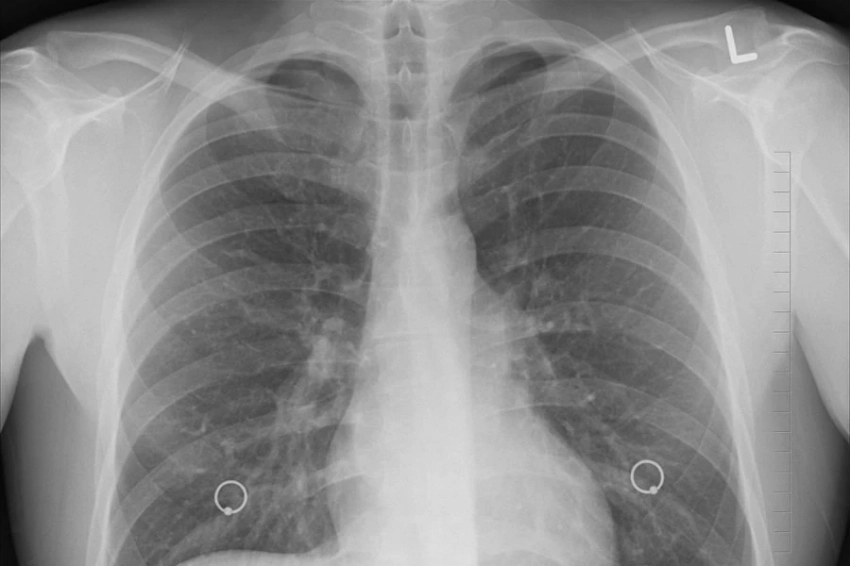

Искусственный интеллект теперь способен определить возраст человека, анализируя рентгеновские снимки грудной клетки. Эту новость сообщает журнал The Lancet.

Исследователи из Высшей школы медицины Осаки (Япония) протестировали модель искусственного интеллекта на 67 099 рентгенограммах грудной клетки. Эти снимки были сделаны в период с 2008 по 2021 год и принадлежали 36 051 здоровому человеку. Модель искусственного интеллекта успешно определила связь между предполагаемым возрастом, вычисленным на основе анализа ИИ, и реальным хронологическим возрастом людей. Коэффициент корреляции составил 0,95, что свидетельствует об очень сильной связи между этими показателями. Дополнительно эксперты использовали 34 197 рентгенограмм грудной клетки от пациентов, у которых уже были диагностированы различные заболевания.

Исследование показало, что разница между возрастом, определенным искусственным интеллектом, и хронологическим возрастом пациента была связана с определенными заболеваниями. Вероятность наличия гипертонии, гиперурикемии и хронической обструктивной болезни легких увеличивалась с ростом предсказанного возраста, полученного ИИ.